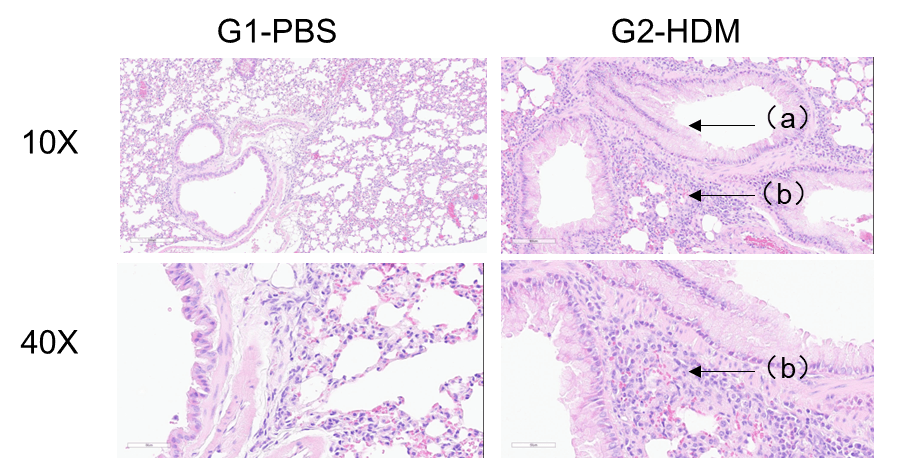

Airway Histology in Asthmatic Mouse Model

OVA successfully induces asthma-related pathology in wild-type C57BL/6 mice. H&E staining of lung tissue shows asthma-related pathology in OVA-treated (G2) mice, including vascular and peribronchial inflammation (b) and mucus (a) accumulation in some bronchi, compared to the untreated (G1) group.

H&E staining of lung tissue in HDM-induced asthmatic C57BL/6 mice. Compared to G1 controls, G2 mice treated with house dust mite (HDM) exhibited characteristic asthma pathology, including vascular and peribronchial inflammatory cell infiltration (b) and mucus production (a). These findings confirm that HDM successfully induces asthma in wild-type C57BL/6 mice.